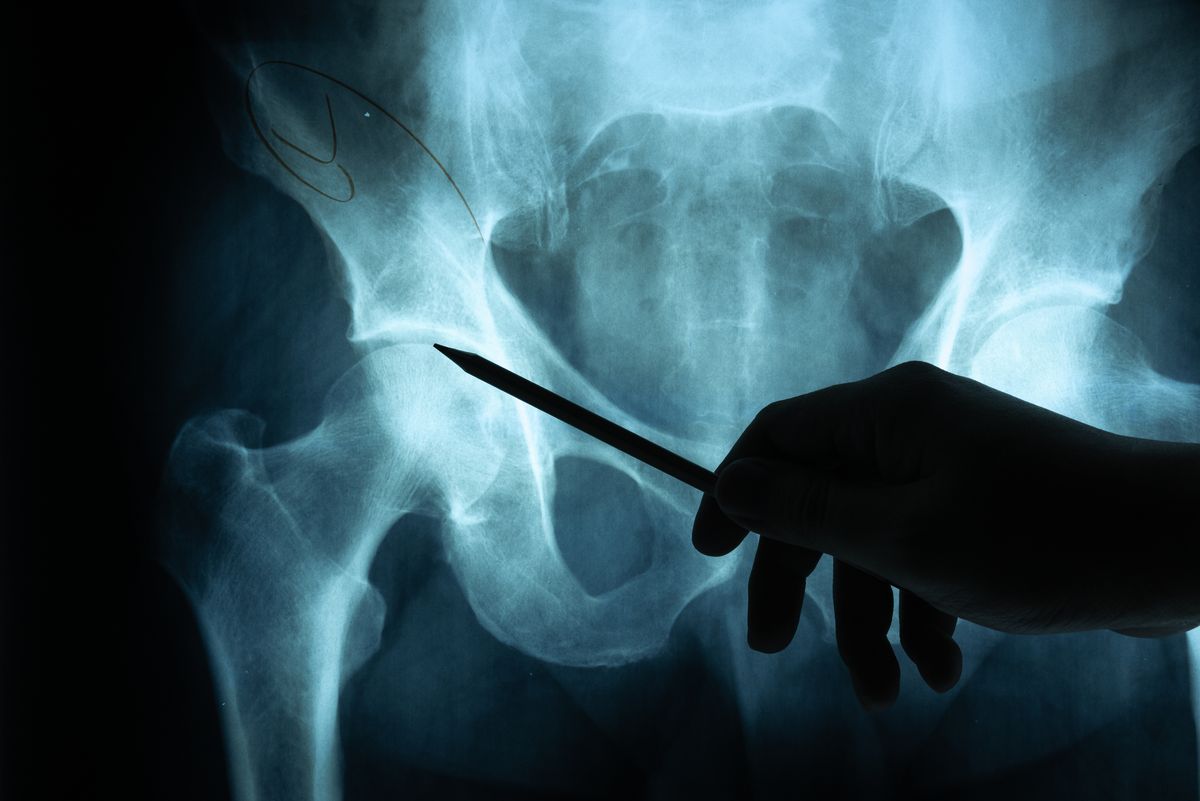

2. больной направляется на рентгенографию или компьютерную томографию;

Чтобы полностью представить картину повреждений, аппаратные исследования проводятся несколько раз с разных ракурсов. По полученным снимкам становится возможным понять тяжесть патологии и выработать правильную методику устранения ее последствий. Она полностью зависит от степени разрушения тазобедренного сустава. При этом, учитываются сопутствующие патологии, например, повреждение седалищного нерва или вывих бедра, которые требуют принятия специальных мер.